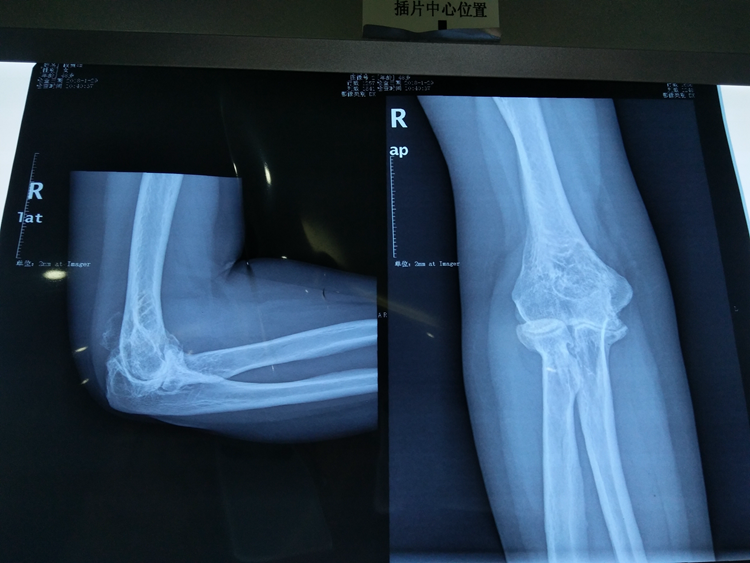

别再让无知害了孩子 ——骨伤科成功救治一名骨折后...